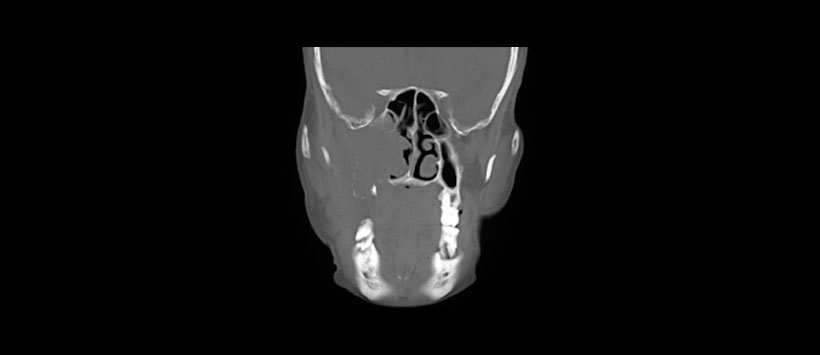

Figura 2: La imagen de TC en corte coronal muestra una gran lesión de densidad de los tejidos blandos con destrucción de todas las paredes del seno maxilar derecho y la extensión hacia la cavidad nasal.